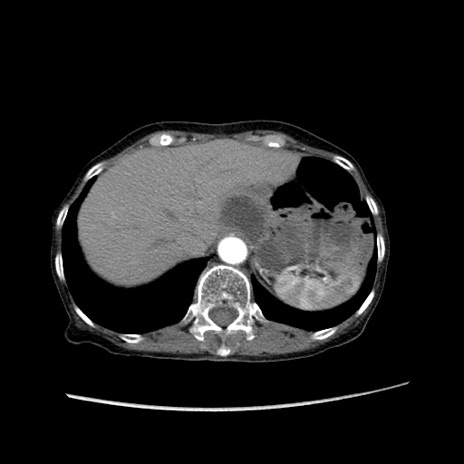

症例25(横断像)

【症例】80歳代女性

【主訴】胸のつかえ感

【現病歴】約9時間前に食後から胸のつかえた感じあり、嘔吐あり、来院。

【既往歴】胃癌(全摘)、胆摘、虫垂炎

【身体所見】心窩部に圧痛あり、反跳痛なし。

【データ】WBC 5700、CRP 0.05